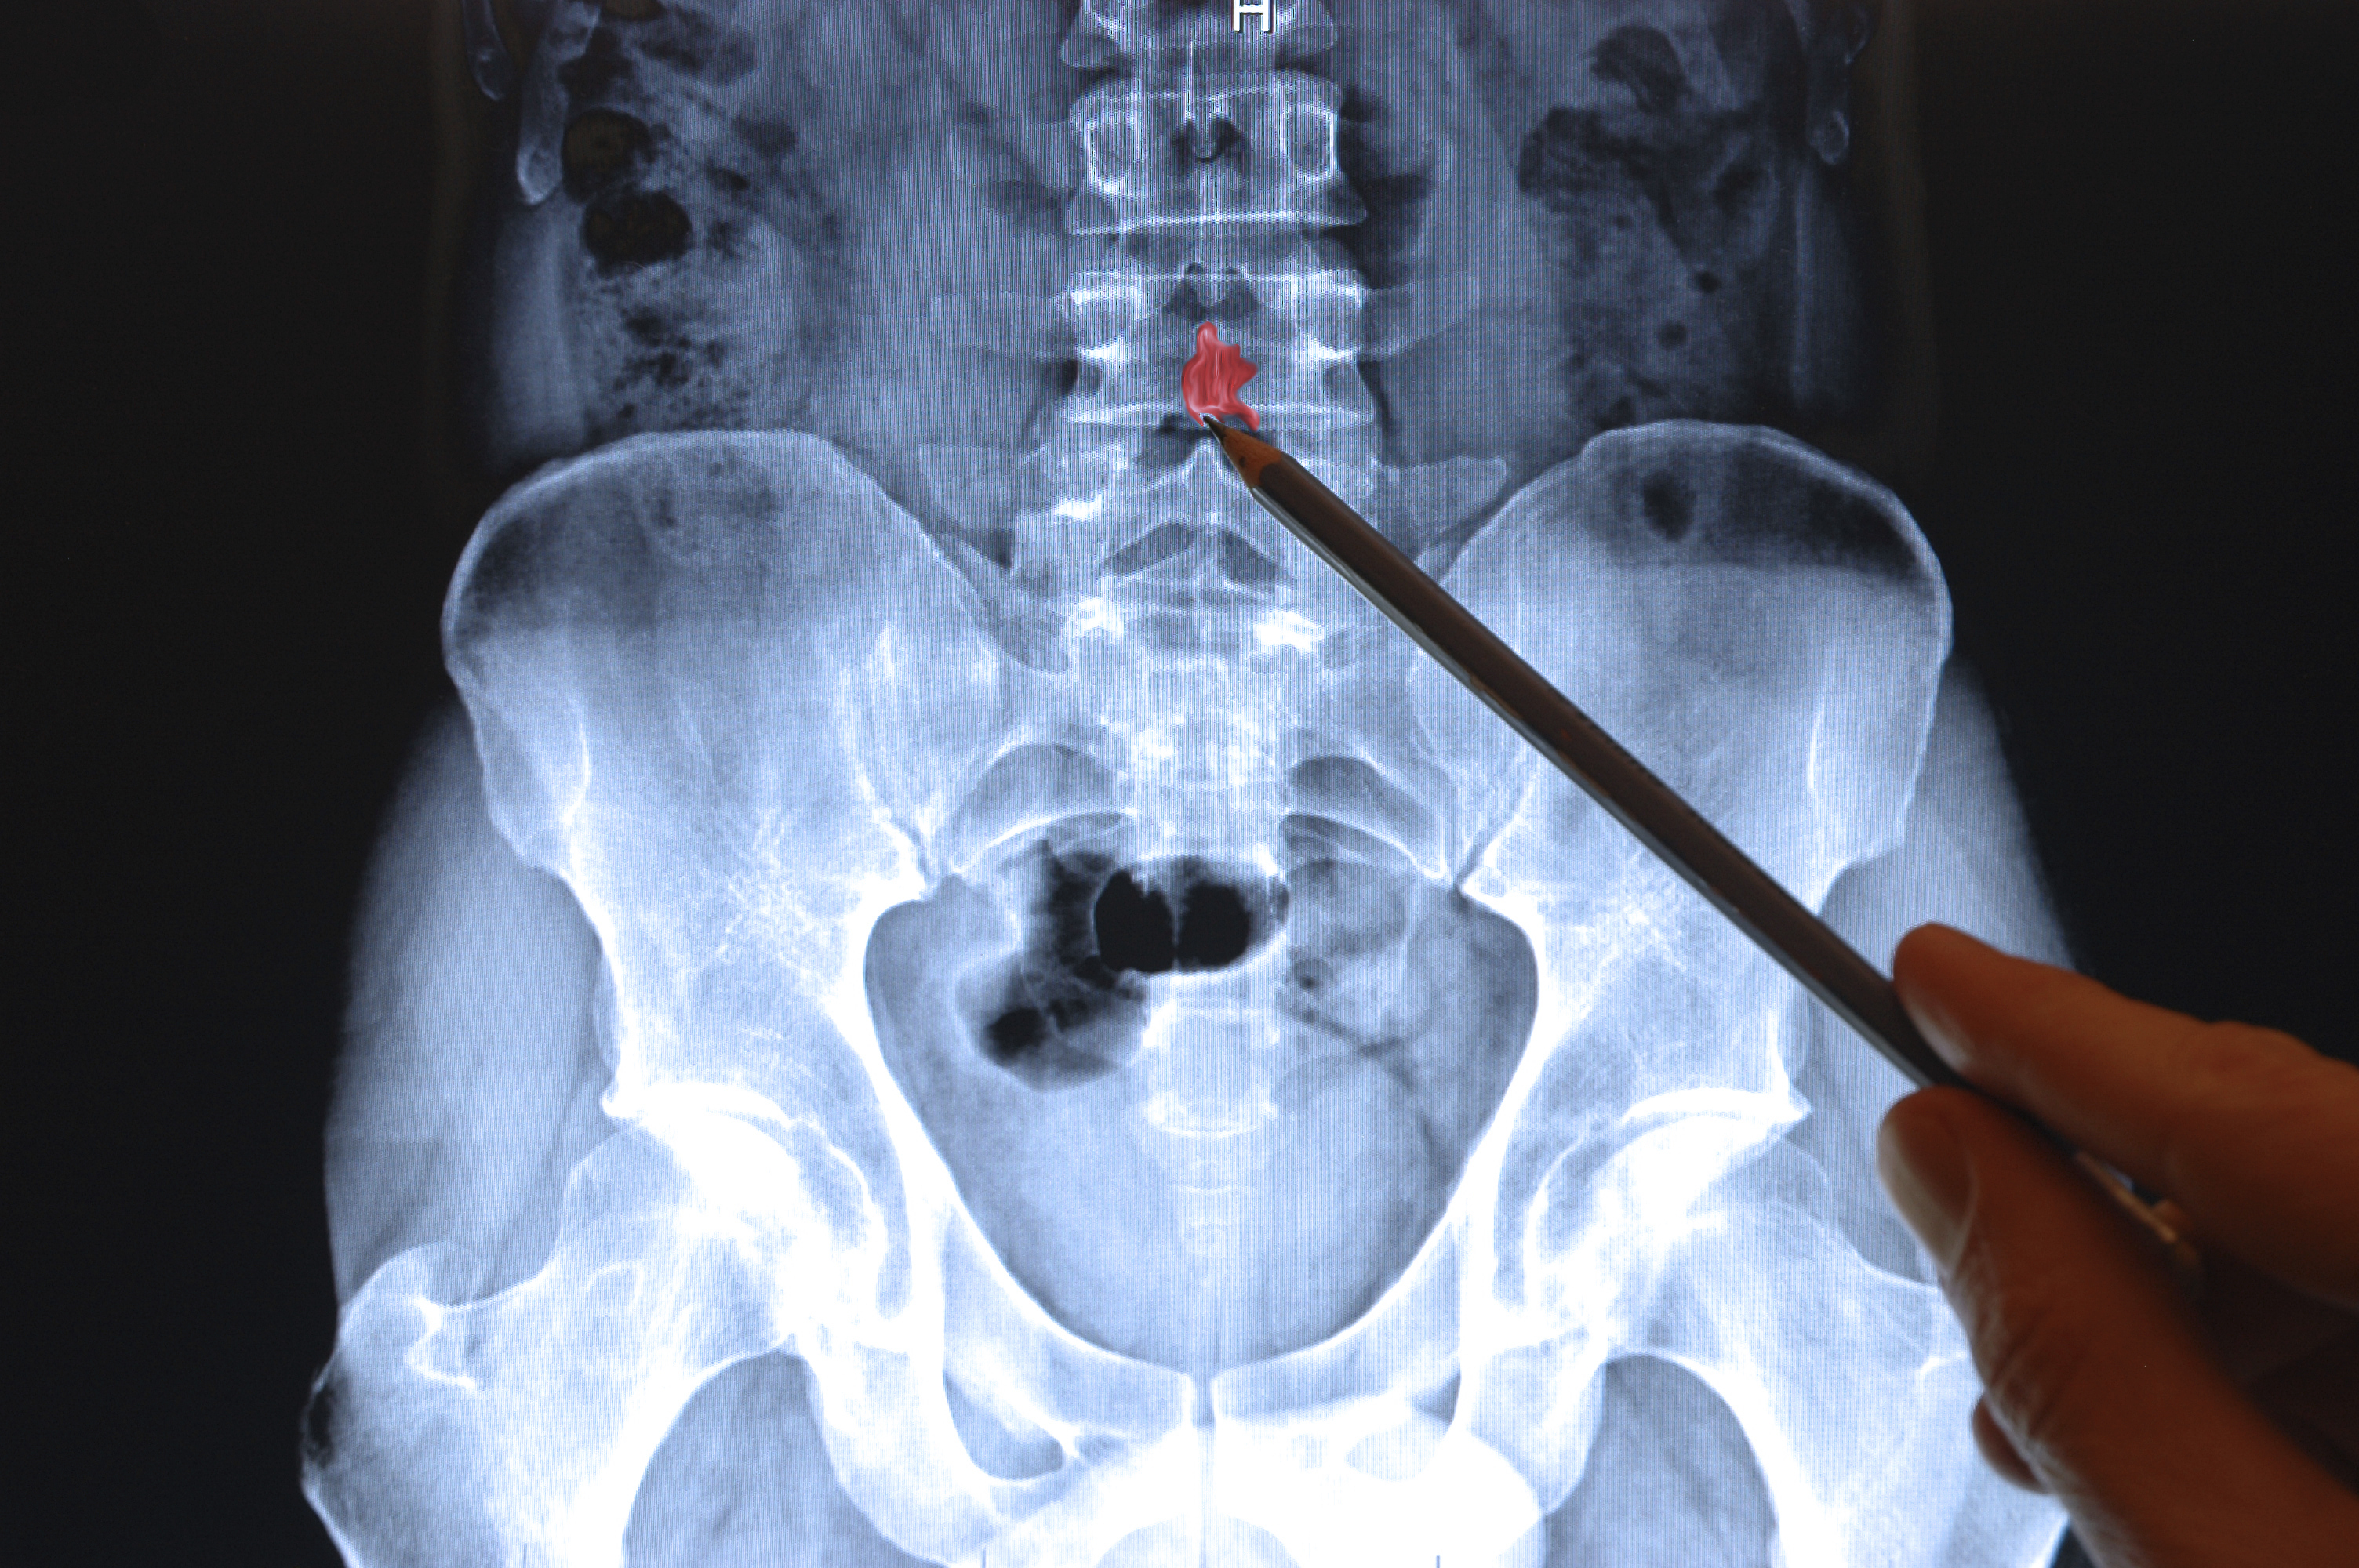

Lombalgia è un termine generico utilizzato per indicare la presenza di un dolore localizzato nella zona lombare della schiena; questa zona è deputata al supporto strutturale, al movimento e alla protezione di alcuni tessuti del corpo.

La struttura della parte bassa della schiena risulta costituita da:

• colonna vertebrale ossea lombare

• dischi tra le vertebre

• legamenti intorno alla spina dorsale e ai dischi

• legamenti intorno al midollo spinale e ai nervi

• muscoli

• organi del bacino e dell'addome

• pelle che copre la zona lombare.

La colonna vertebrale ossea lombare è fatta in modo che le vertebre possano fornire una struttura mobile volta a proteggere il midollo spinale. Il midollo spinale è composto da un tessuto nervoso che si estende lungo la colonna vertebrale partendo dal cervello.

Ogni vertebra ha un processo spinoso, ossia una prominenza ossea alla base del midollo spinale, pertanto le vertebre hanno un corpo vertebrale. I dischi vertebrali sono "pastiglie" che fungono da "cuscinetti" tra i singoli corpi vertebrali, questi aiutano a ridurre al minimo l'impatto delle forze di stress sulla colonna vertebrale.

Di solito, l'esame a raggi X è solo utile per escludere anomalie delle ossa. I nervi della colonna lombare possono essere irritati dalla pressione meccanica, da altri tessuti o da malattia. Queste condizioni comprendono la malattia del disco lombare (radicolopatia), l'invasione ossea e l'infiammazione dei nervi causata da una infezione virale (herpes zoster).